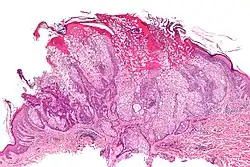

Micrograph of a sebaceous adenoma, as may be seen in Muir–Torre syndrome. H&E stain.

Muir–Torre syndrome is a rare hereditary, autosomal dominant cancer syndrome[1]: 663  that is thought to be a subtype of HNPCC (Lynch syndrome). Individuals are prone to develop cancers of the colon, genitourinary tract, and skin lesions, such as keratoacanthomas and sebaceous tumors. The genes affected are MLH1,[2] MSH2,[3] and more recently, MSH6,[4] and are involved in DNA mismatch repair.